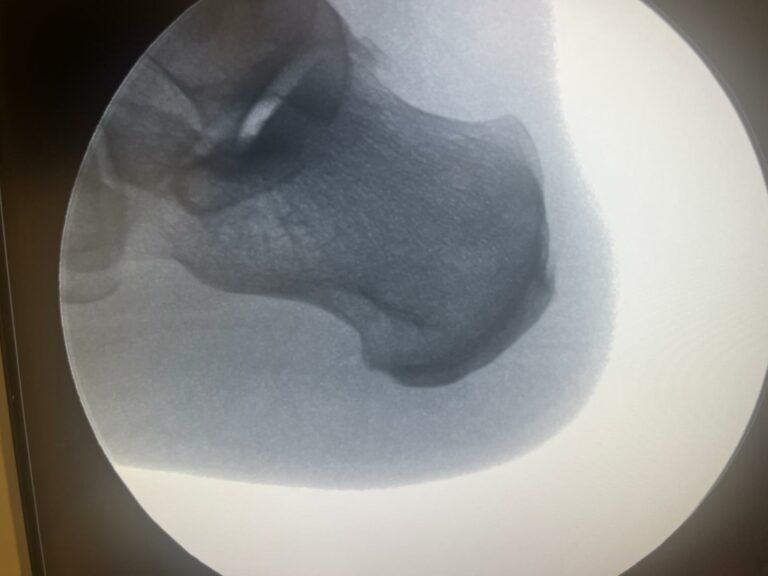

El espolón calcáneo es una calcificación ósea en la parte inferior del talón que puede causar un dolor punzante. Esta afección suele estar relacionada con la fascitis plantar, una inflamación del tejido que conecta el talón con los dedos del pie.

En Clínica Arriaga, realizamos la cirugía de espolón calcáneo mediante la técnica MIS, un procedimiento ambulatorio con mínima invasión que elimina la calcificación ósea de manera precisa.

El tratamiento se realiza bajo anestesia local y sin necesidad de hospitalización, permitiendo al paciente regresar a su domicilio el mismo día. Gracias a este método, la recuperación es más rápida y con menos molestias en comparación con técnicas tradicionales.